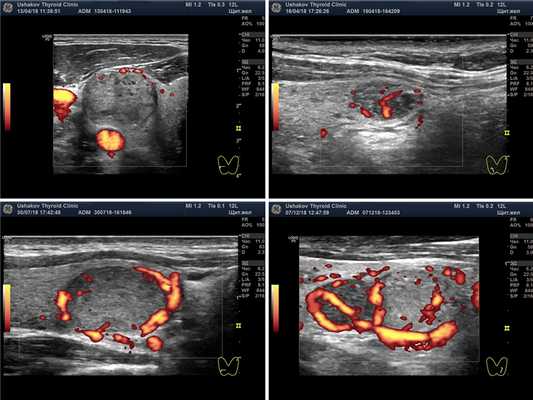

Рисунок. 6. Интенсивность кровотока узлов щитовидной железы. Показаны несколько вариантов интенсивности кровотока: Малой интенсивности, Умеренной интенсивности, Значительной интенсивности.

Сосуды узла могут определяться по периметру и внутри узла. Информация о том, что кровоток узла «смешанный» (то есть внутри и вокруг узла) не имеет особой клинической ценности, так как может также часто встречаться как в доброкачественных, так и в злокачественных узлах.